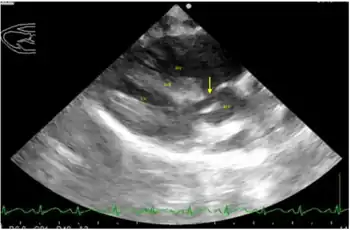

Right parasternal long axis left ventricular outflow tract view of heart with ventricular septal defect and overriding aorta